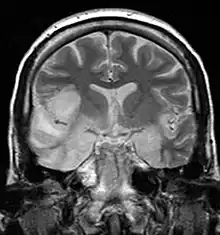

| Herpesviral encephalitis and herpesviral meningitis | Herpes simplex encephalitis (HSE) is a rare life-threatening condition that is thought to be caused by the transmission of HSV-1 either from the nasal cavity to the brain's temporal lobe or from a peripheral site on the face, along the trigeminal nerve axon, to the brainstem.[19][20][21][22] Despite its low incidence, HSE is the most common sporadic fatal encephalitis worldwide. HSV-2 is the most common cause of Mollaret's meningitis, a type of recurrent viral meningitis. |  |